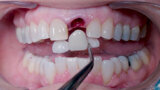

Fig. 5: Initial osteotomy with needle drill.